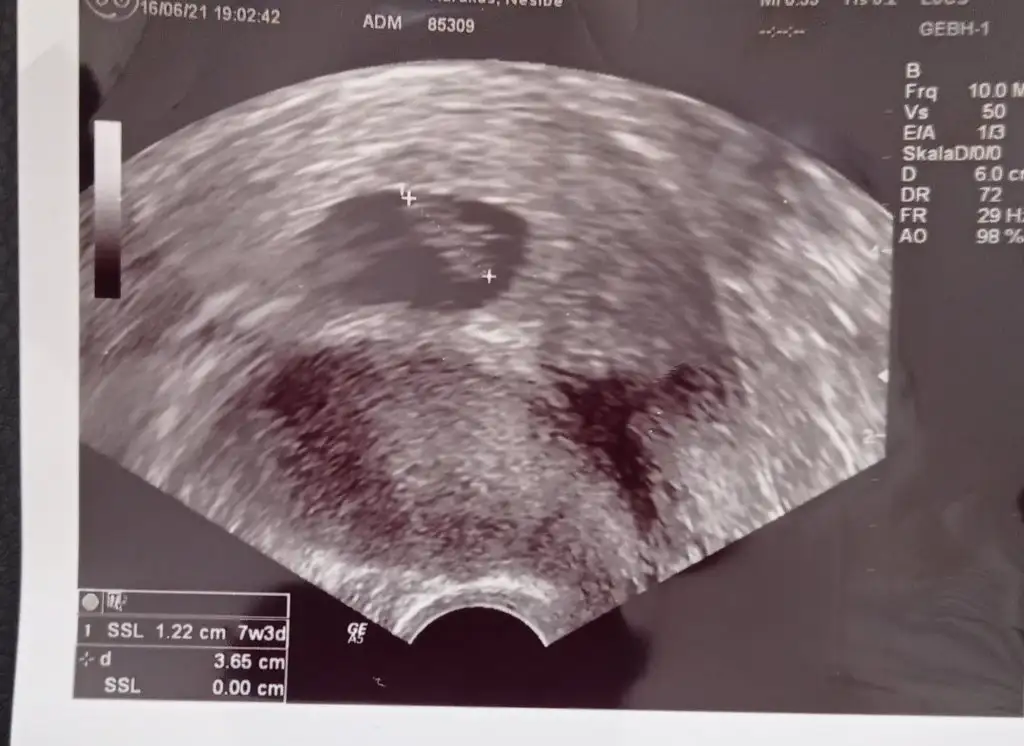

Kizlar 11 haftalık, yorum yapar misiniz? 🙏😊Her ne kadar sağlıklı olsun gerisi önemli değil desek de merak ediyoruz🙈

Eklentiler

• 16232530652464313464340824964686.webp

16232530652464313464340824964686.webp

21,6 KB · Görüntüleme: 66